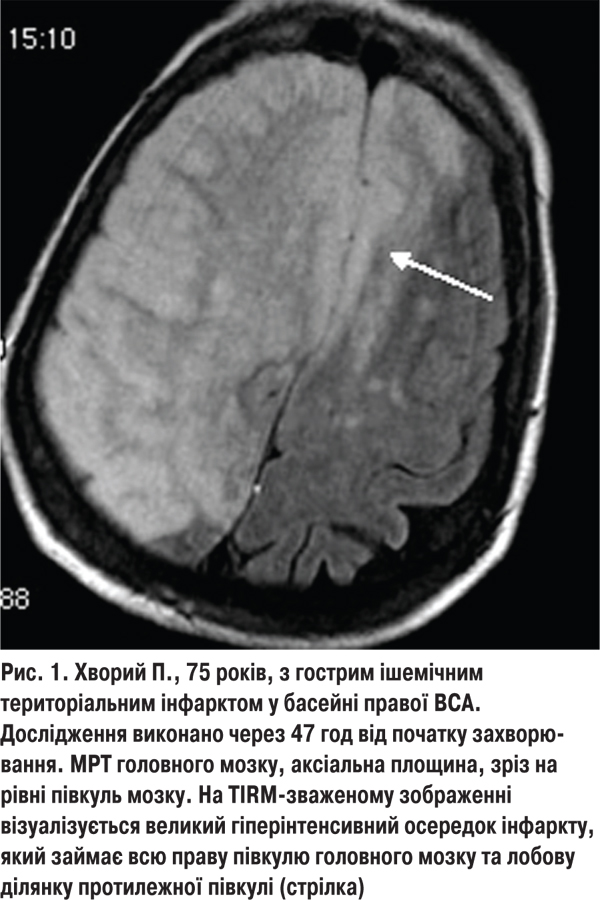

У 16 (11,4%) хворих 2-ї групи ішемічний інсульт був зумовлений ураженням великих магістральних судин голови в екстракраніальному відділі. У них відзначали ознаки порушення функцій не лише кірково-підкіркових структур, а навіть всієї півкулі головного мозку (рис. 1). Виражений неврологічний дефіцит виявляли і в разі ураження основного стовбура СМА або інтракраніального відділу внутрішньої сонної артерії (ВСА) (територіальний інсульт). У 104 (74,3%) хворих із фатальними наслідками інсульту вогнище інфаркту займало більше половини території кровопостачання СМА. Великовогнищевий інфаркт призводив до вимушеної нерухомості хворого, що значно підвищувало ризик розвитку медичних ускладнень, які погіршували перебіг та наслідки захворювання. Ще у 20 (14,3%) пацієнтів із фатальними наслідками велике ішемічне вогнище із середніми розмірами 45,7±9,8 см3 локалізувалося у стовбурі головного мозку, що призводило до порушення життєвоважливих функцій та їх смерті в 1-шу добу захворювання.